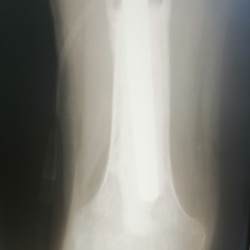

Пациент 1988 года рождения. Имеется рана с выделением на уровне перелома большеберцовой кости. Были переломы. Посттравматический остеомиелит?